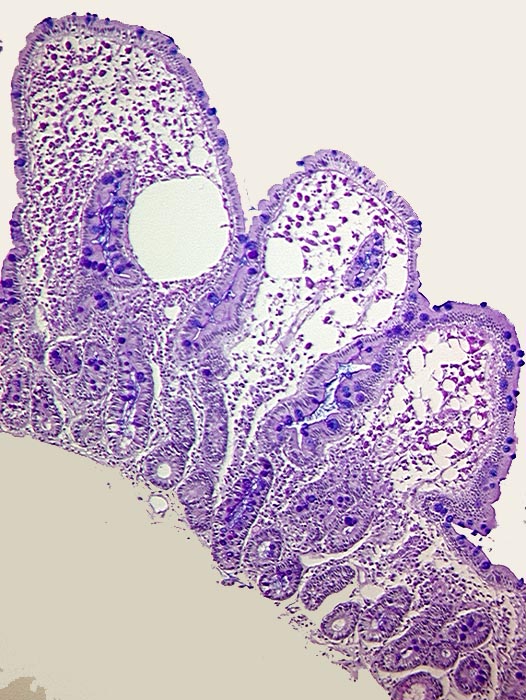

PathoPic ID 436 - Morbus Whipple

Morbus Whipple

Entzündung infektiös

Dünndarm

Darm, Anus

Ektatisches Lymphgefäss in der Dünndarmzotten und massenhaft PAS positive Makrophagen im Stroma.

Elektronenmikroskopisch Stäbchenbakterien in den Makrophagen. Ziehl Neelsen negativ.

Histologie